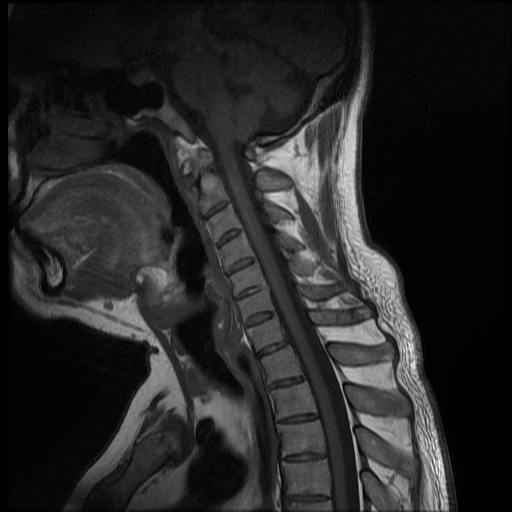

Se observa perdida de la lordosis normal de la columna cervical.

Se observa hipo intensidad del ligamento longitudinal anterior y posterior de la columna cervical, también se observa perdida de la movilidad y rigidez de la misma, los ligamentos interespinosos se ven hipointensos en T2 y en T1, al igual que el pliegue nucal, lo que sugiere calcificación de estas estructuras anatómicas.

Se observa fusión de las vertebras cervicales 5-6 y 6-7, dando la apariencia de bambú.